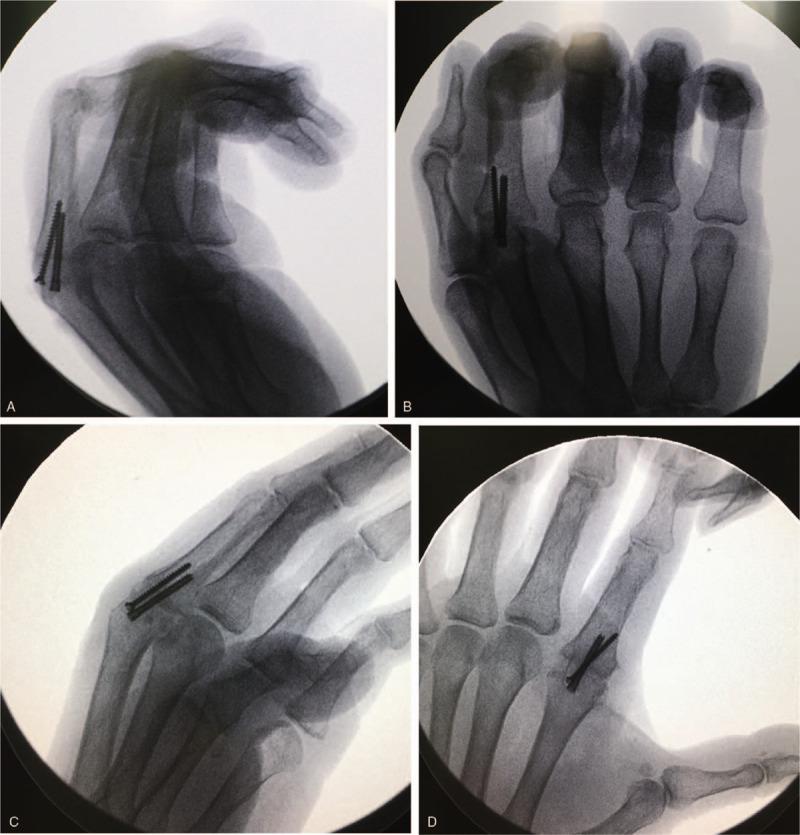

Based on the combination of physical examination, X-ray, and ultrasonic and magnetic resonance imaging, the patient was diagnosed with bilateral tear of the RCLs and joint dislocation of the index MCP joint. Eventually, intra-operative findings confirmed the diagnosis.

INTERVENTION

The patient underwent bilateral index MCP joint fusion followed by immobilization for 6 weeks. Functional therapy was started after immobilization.

结合体格检查、X线、超声及磁共振成像,患者被诊断为双侧RCL撕裂及示指掌指关节脱位。最终,术中所见证实了诊断。

干预

患者接受了双侧示指掌指关节融合术,随后固定6周。固定后开始功能治疗。